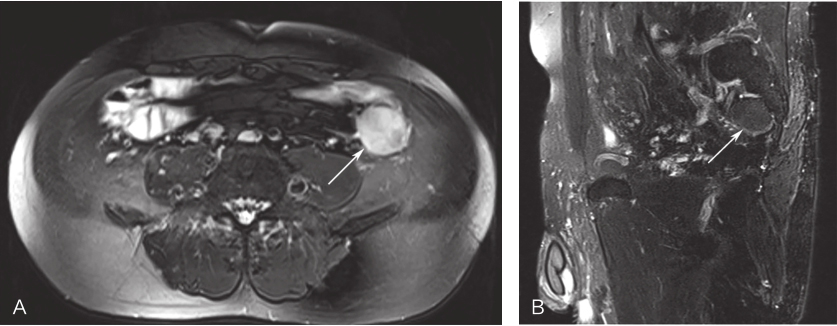

全腹增强MRI:左下腹见一类圆形异常信号影,考虑结肠间质来源肿瘤;脂肪肝;胆囊多发结石;双肾多发囊肿(图1)。

图1 腹部MRI

A.横断面;B.矢状面,左下腹见一类圆形异常信号影,结肠GIST